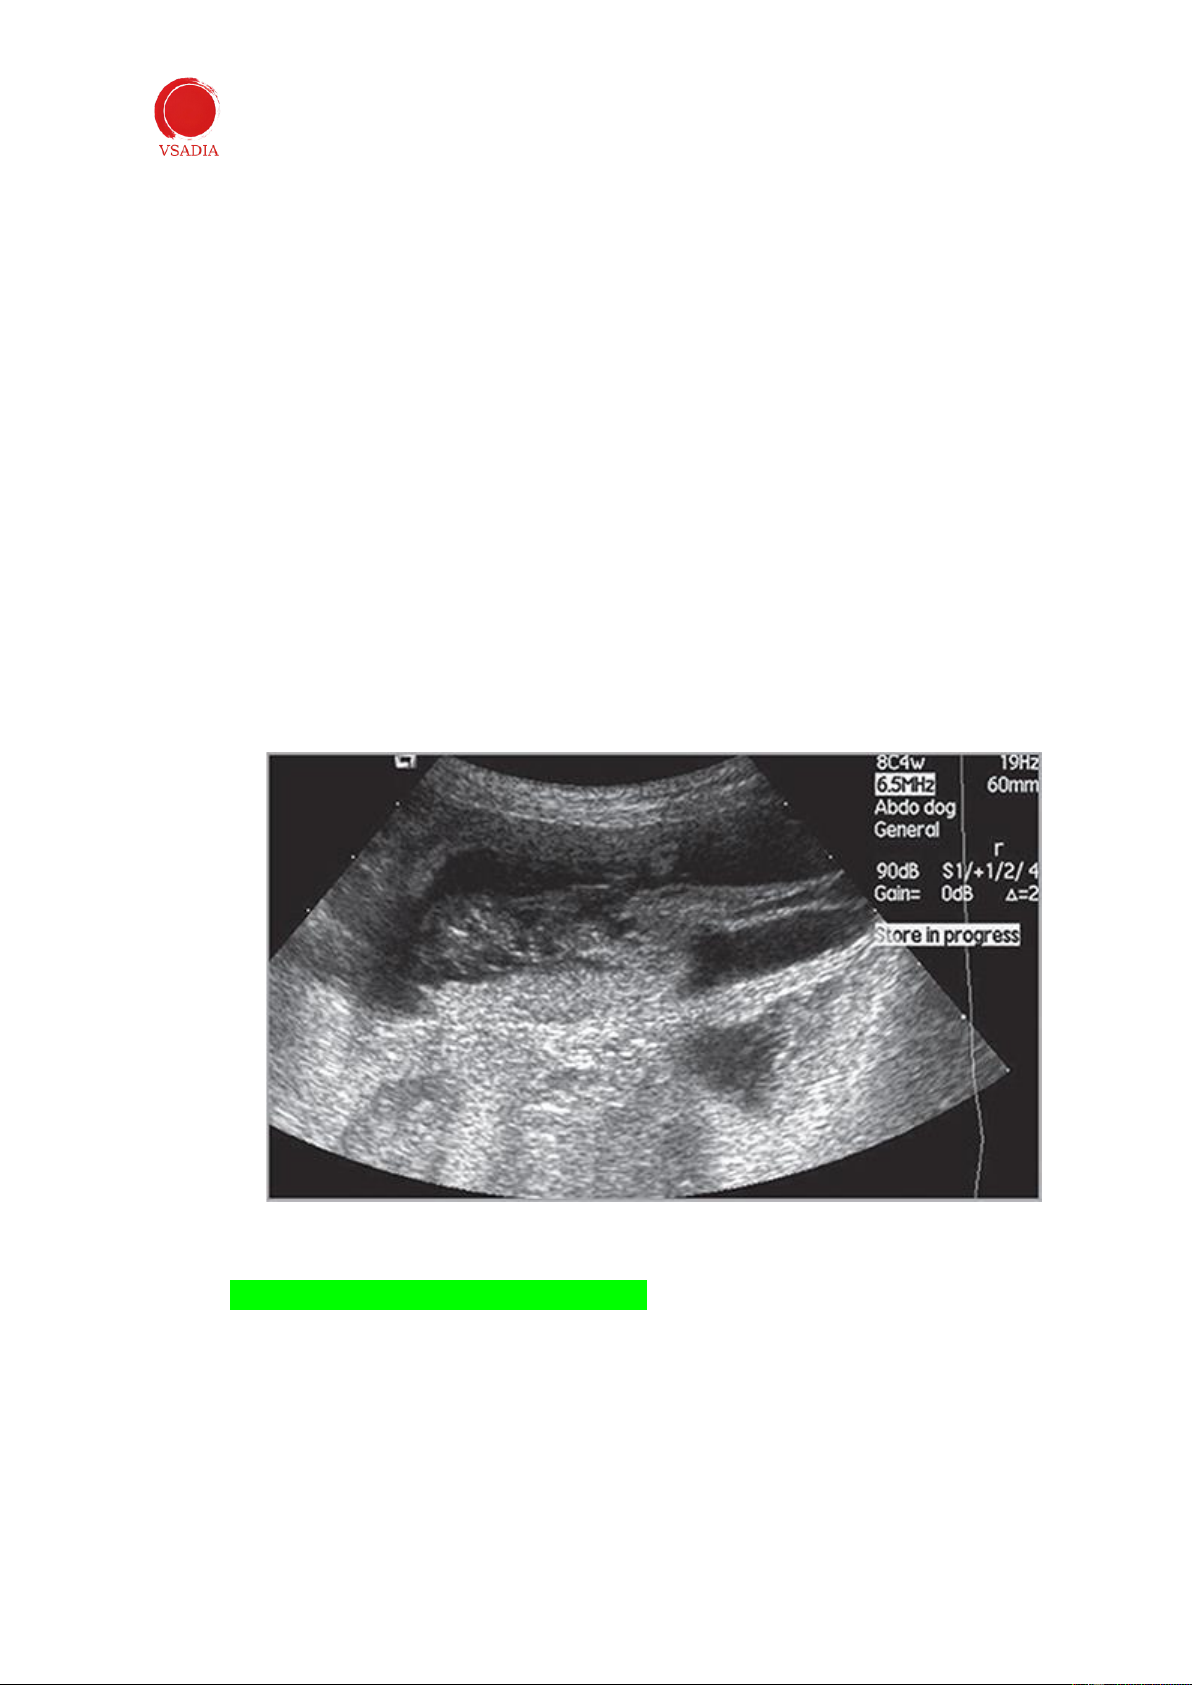

Khi có mủ tử cung, tử cung và sừng tử cung to ra và chứa đầy dịch (Hình 12). Sự mở

rộng này thường đối xứng, mặc dù những thay đổi khu trú hoặc từng đoạn cũng có thể

được xác định. Nội dung tử cung có thể không có tiếng vang hoặc tiếng vang. Mủ tử

cung phải được phân biệt với niêm mạc, máu tích tụ và nước, có hình dạng siêu âm tương tự (Bảng 1).

Hình 12: Mủ tử cung ở một con chó. Tử cung (*) có vẻ giãn ra và chứa đầy dịch. UB: bàng quang tiết niệu.